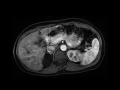

Adrenal cyst

MRI images demonstrate a simple appearing left adrenal T2 bright cyst without internal enhancement.